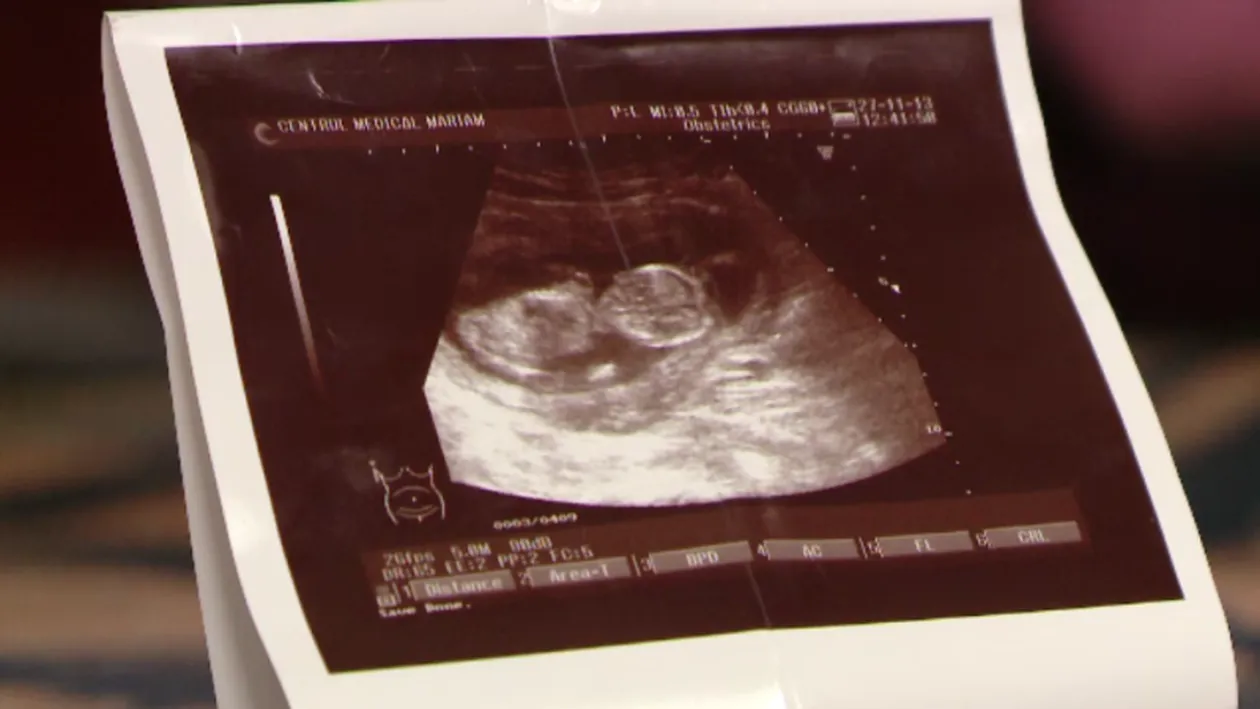

Adelina Socaciu, o graviduţă din Timişoara, a mers la medic pentru a-şi face chiuretaj. Câteva zile mai târziu a descoperit că era tot însărcinată, iar explicaţia e una copleşitoare.

“Doamna doctor spune ca mi-a facut chiuretajul, dar se poate sa fi avut gemeni si sa fi scos doar un fat iar, al doilea sa fi ramas”, povesteste Adelina Socaciu.

Femeia este convinsă că ar fi avut o sarcină dublă, deşi ecografia făcută înainte de intervenţie nu arăta o sarcină dublă. Medicul s-a oferit să îşi repare greşeala şi să termine intervenţia gratuit. Graviduţa însă a refuzat şi a decis să păstreze bebeluşul, urmand sa i se faca analize suplimentare pentru a vedea daca sanatatea micutului a fost sau nu afectata de tratamentul cu antibiotice.